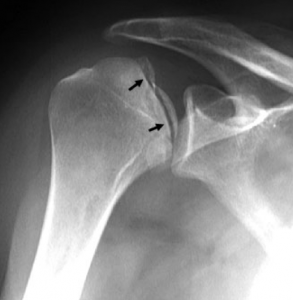

Een goed klinisch onderzoek door de arts is essentieel om de diagnose te vermoeden en op te sporen of er sprake kan zijn van begeleidende zenuw letsels. Een klassieke radiografie toont de ontwrichting en ook eventuele bijkomende letsels bv. breuken. In tweede fase en zeker bij recidiverende ontwrichtingen zal bijkomend een CT scan of MRI scan met contrast gepland worden om de schade aan het kapsel, de ligamenten en het labrum in beeld te brengen.

- Een klassieke radiografie toont de ontwrichting en ook eventuele bijkomende letsels bv. breuken